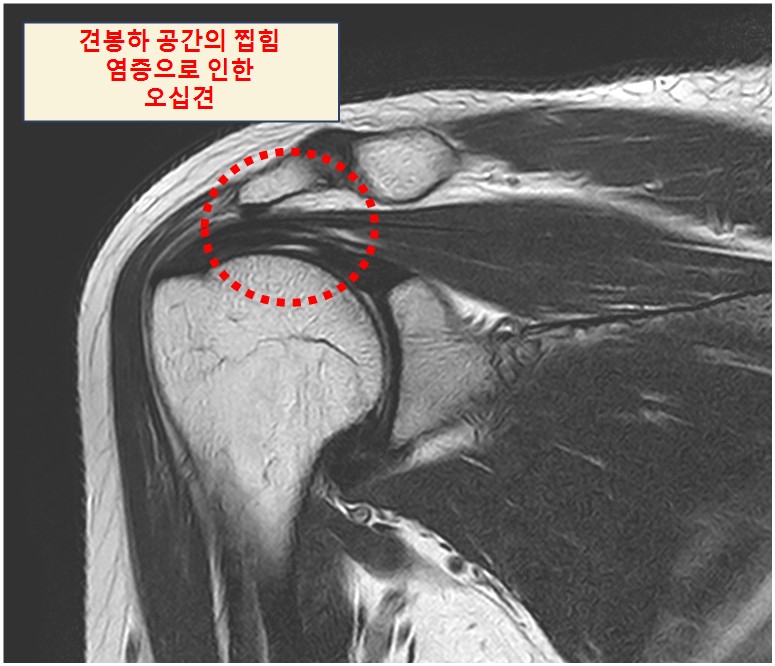

오십견은 진단 용어(의학용어)로는 유착성 관절낭염으로 어깨 관절을 둘러싸고 있는 관절낭에 생긴 염증으로 두꺼워지고 서로 달라붙어 팔의 움직임 제한과 통증을 유발합니다. 주로 40대 후반에서 50대에 발생하고 여성에서 흔하며 팔이나 팔꿈치 골절 등으로 1주 이상 어깨를 사용하지 않는 경우 오십견으로 이어질 수 있습니다.

이 근육들은 팔을 올릴때 어깨뼈와 근육 사이 찝힘이 나타나면서 근육이나 힘줄에 구멍이 생기고 부분파열이 점차 커지는 상황을 회전근개 파열이라고 말하고 있으며 주로 팔을 올릴 때 작용하는 극상근(Supraspinatus muscle)의 찢김에 의해 발생합니다.

오십견의 경우 팔을 올릴 때 끝부분에서 통증이 있다면 회전근개 파열은 수동적으로는 팔을 끝범위까지 올릴 수 있지만 스스로 근육의 힘으로 팔을 올릴 경우 중간 범위부터 통증이 발생합니다.